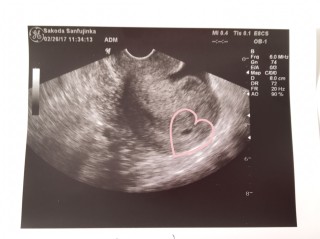

写真:5w2d:どんぐりさん

過去に2回流産しており、不安な妊婦生活を送っていますが、無事に12.2mmの胎嚢を確認することができました!写真だと分かりづらいけど、卵黄囊も見えました。過去2回の妊娠と比べても、いちばん順調な大きさ。先生のリアクション的にも順調なのかな!今度こそ産んであげたいです。